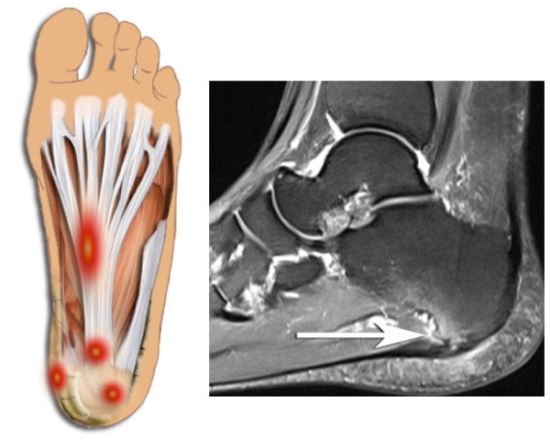

족저근막염이란?

발 뒤꿈치에서부터 발바닥 앞쪽까지의 발바닥 근육을 감싸고 있는 두꺼운 근막이 "족저근막"이라고 합니다. 족저근막이 발바닥의 아치를 유지하고, 걸을 때 스프링처럼 완충 작용을 하여 발을 보호해 주는 기능을 하는데, 이 족저 근막에 반복적인 미세 손상을 입어 염증이 발생한 것을 "족저근막염"이라고 합니다. 대게 40~50대의 여성에게 많이 발생합니다.